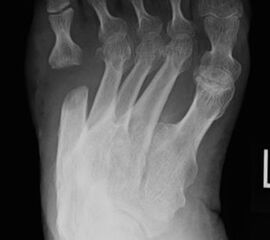

Abb. 8 a, b, c: Typ III Deformität mit prä- (a) und postoperativem Röntgenbild (b, c) mit Schrauben-Osteosynthese.